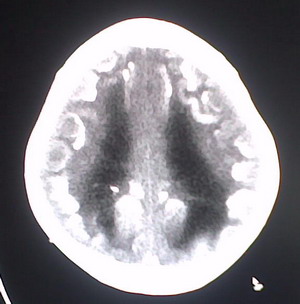

以下是引用jiajie在2009-2-3 20:02:00的发言:[br]脑室周围白质区可见大量斑片状钙化,部分融合成带状,双侧侧脑室及第三脑室扩大。[br]考虑弓形体原虫感染。(先天性宫内感染、torch综合症)

以下是引用lkc8963在2009-2-3 21:15:00的发言:[br]临床眼睑可见静脉扩张,ct双侧眼上静脉亦示扩张,颅内钙化以皮层\\软脑膜为主而不是位于白质和室管膜,再加上静脉窦异常,还是应该考虑静脉血管瘤病,可能为较复杂的血管畸形.

以下是引用卜一在2009-2-4 9:21:00的发言:[br]sturge-weber综合征:面部三叉神经分布区的毛细血管性或海绵状血管瘤以及同侧枕、顶或额叶软脑膜的血管瘤(以静脉性为主)。脑皮质,特别是第二三层,毛细血管可有增厚和钙化。局部发生层状坏死、神经细胞脱失、萎缩、胶质细胞增生及钙盐沉着。可根据面部典型分布的特征性皮痣作出诊断。头颅ct:发现面部血管瘤同侧的脑内病理钙化影,呈双层线条波浪形、脑回形或树枝形。本例支持:sturge-weber综合征![br]